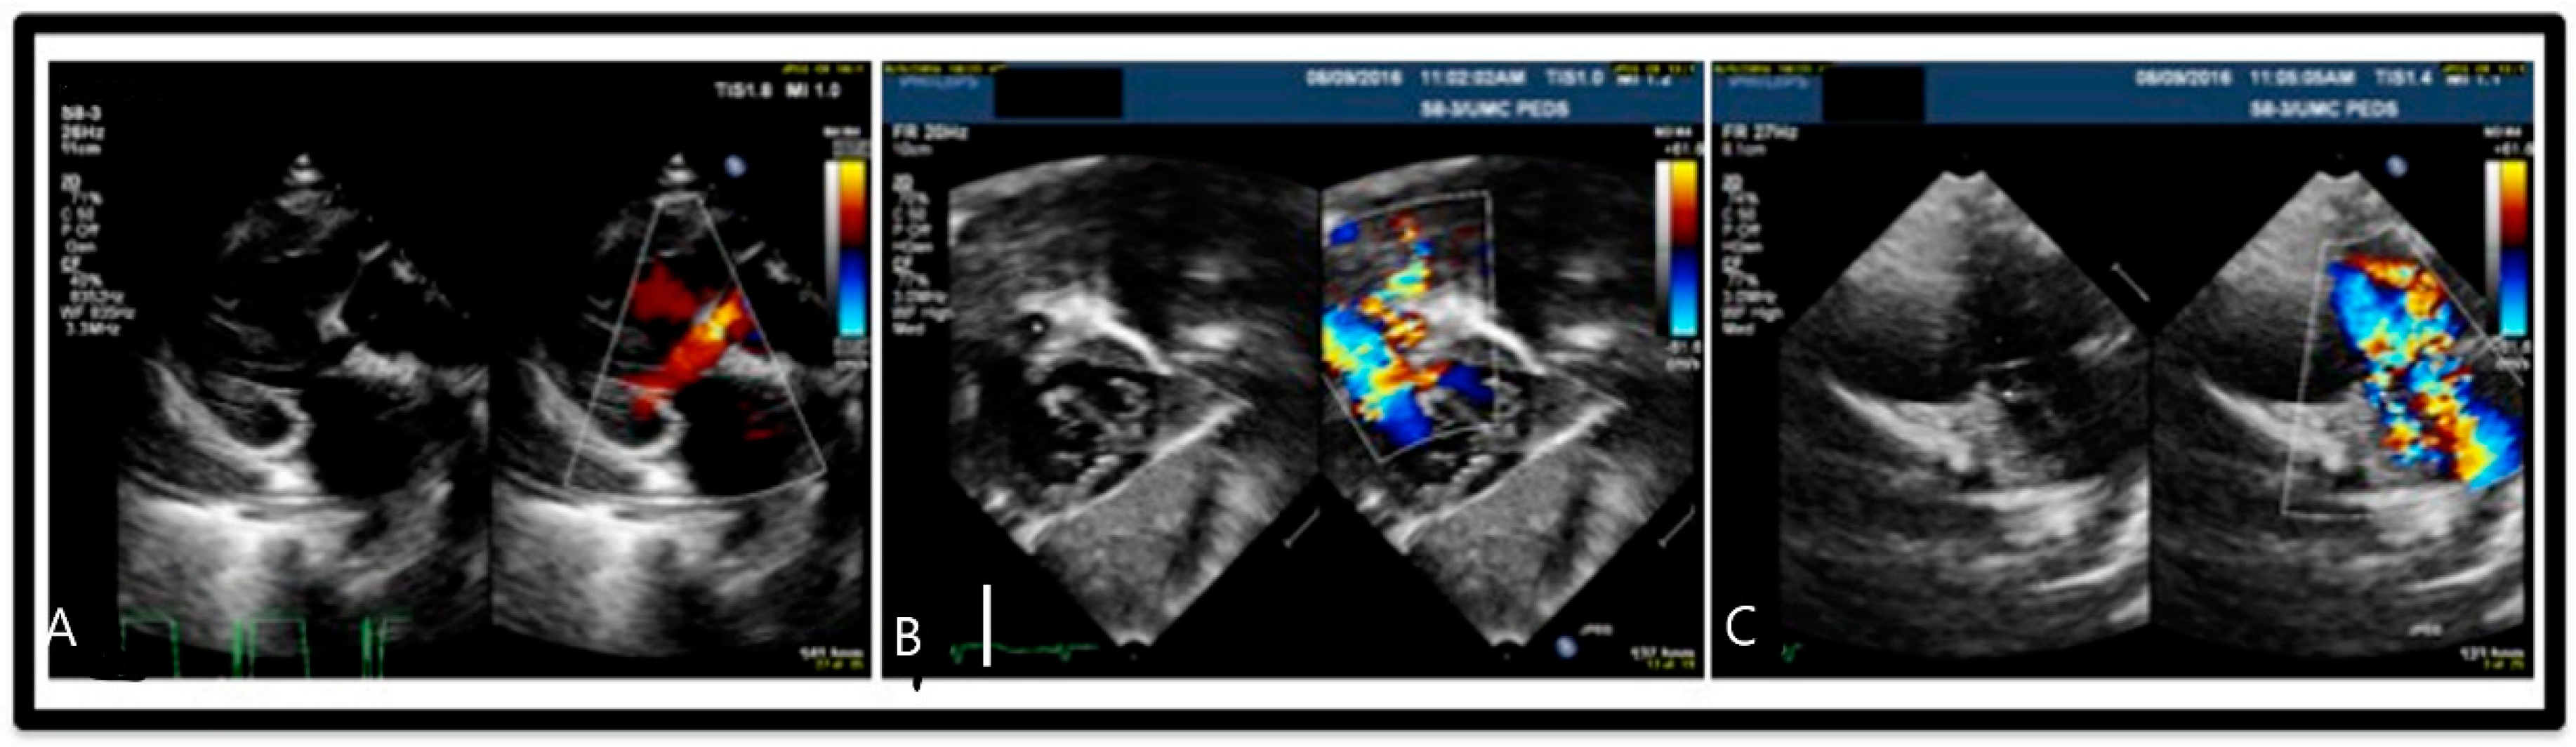

Figure 2.

Echocardiogram: (A) Long axis view of ventricular septal defect (VSD) demonstrating pulmonary vessel stenosis. (B) Subcostal four chamber view of VSD with aorta overriding pulmonary artery and feeding into right ventricle. (C) View of double outlet pulmonary artery and aorta from right ventricle with VSD present.